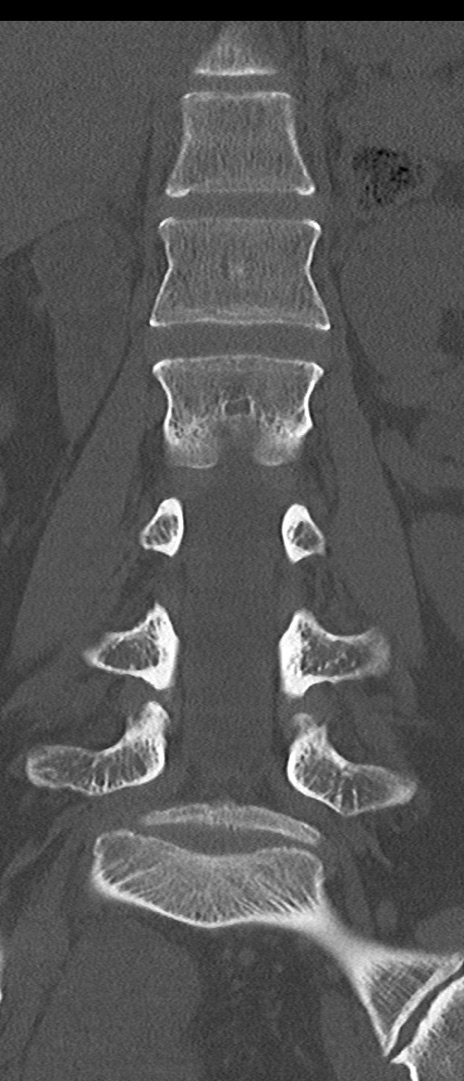

【整形】TIPS症例4 腰椎CT(冠状断像)

腰椎CT